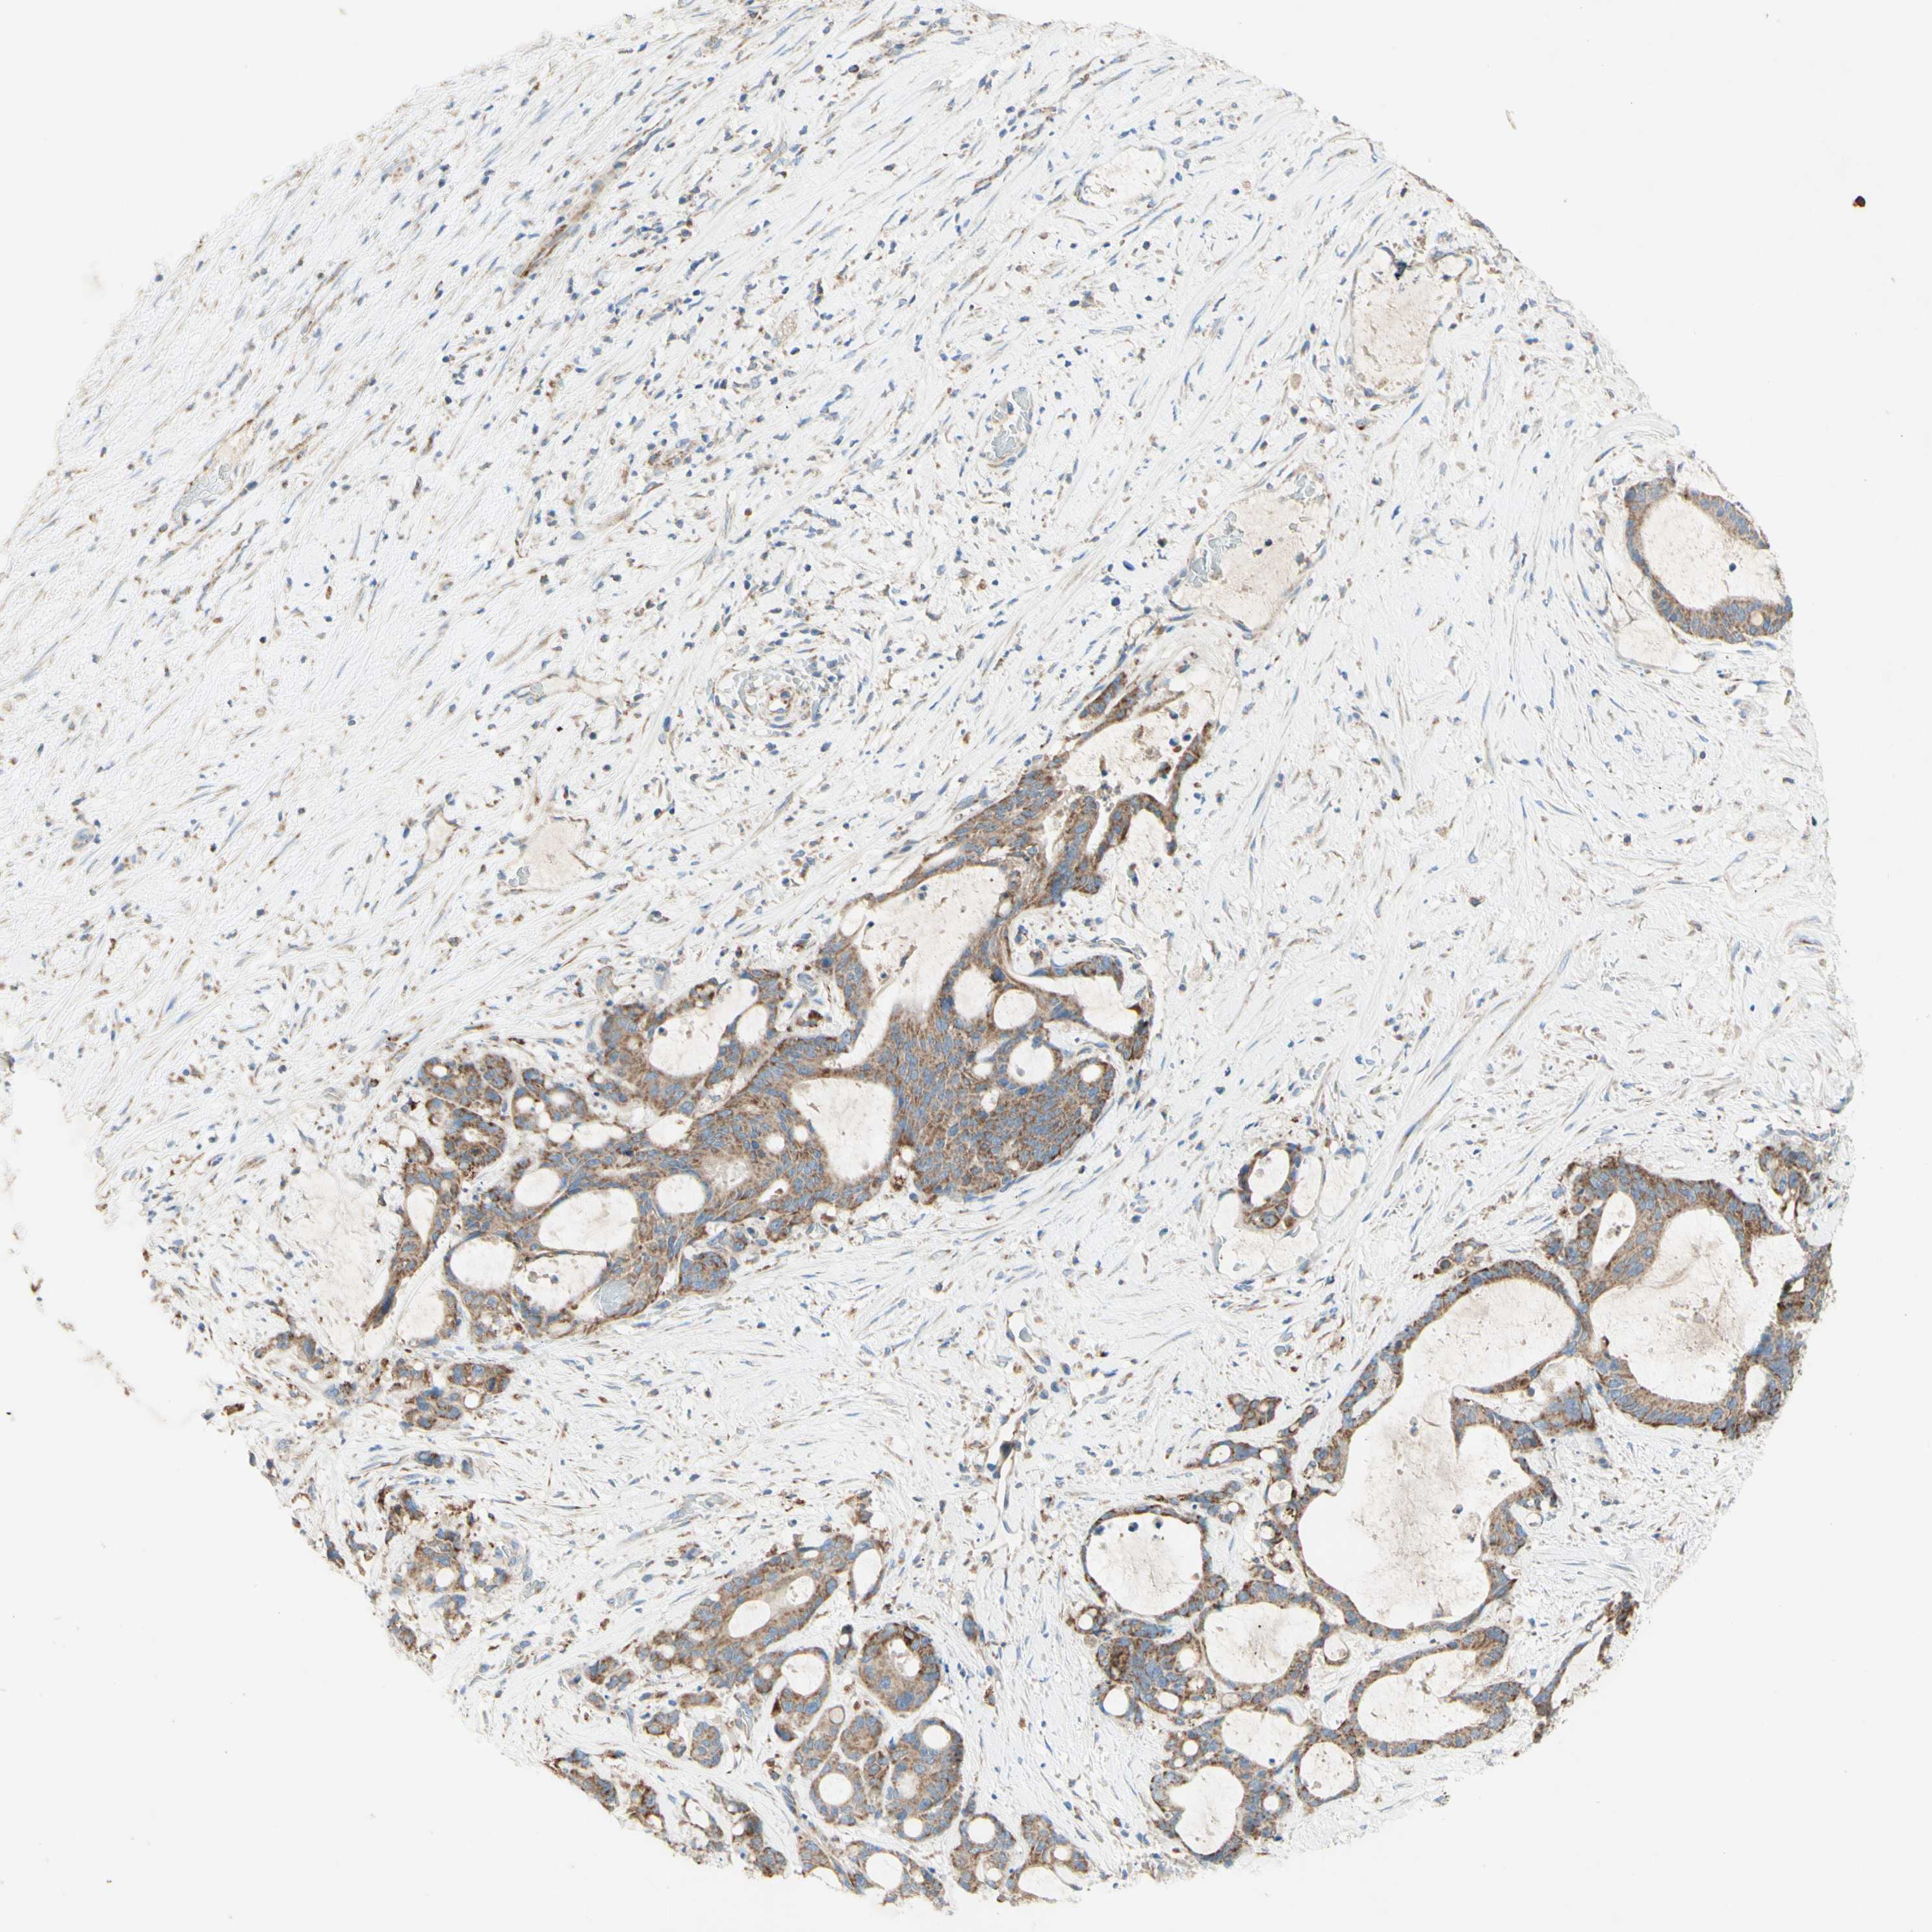

LIVER CANCER - Protein expressioni

A mouse-over function shows sample information and annotation data. Click on an image to view it in a full screen mode. Samples can be filtered based on level of antibody staining by selecting one or several of the following categories: high, medium, low and not detected. The assay and annotation is described here.

Antibody stainingi

Antibody staining in the annotated cell types in the current human tissue is reported as not detected, low, medium, or high, based on conventional immunohistochemistry profiling in selected tissues. This score is based on the combination of the staining intensity and fraction of stained cells.

Each image is clickable and will lead to virtual microscopy that enables deeper exploration of all samples and also displays staining intensity scores, fraction scores and subcellular localization as well as patient and tissue information for each sample.

Antibody HPA011036

Antibody HPA011057

Staining

High

Medium

Low

Not detected

Intensity

Strong

Moderate

Weak

Negative

Quantity

>75%

75%-25%

<25%

None

Location

Nuclear

Cytoplasmic/membranous

Cytoplasmic/membranous,nuclear

Cholangiocarcinoma

Carcinoma, Hepatocellular, NOS